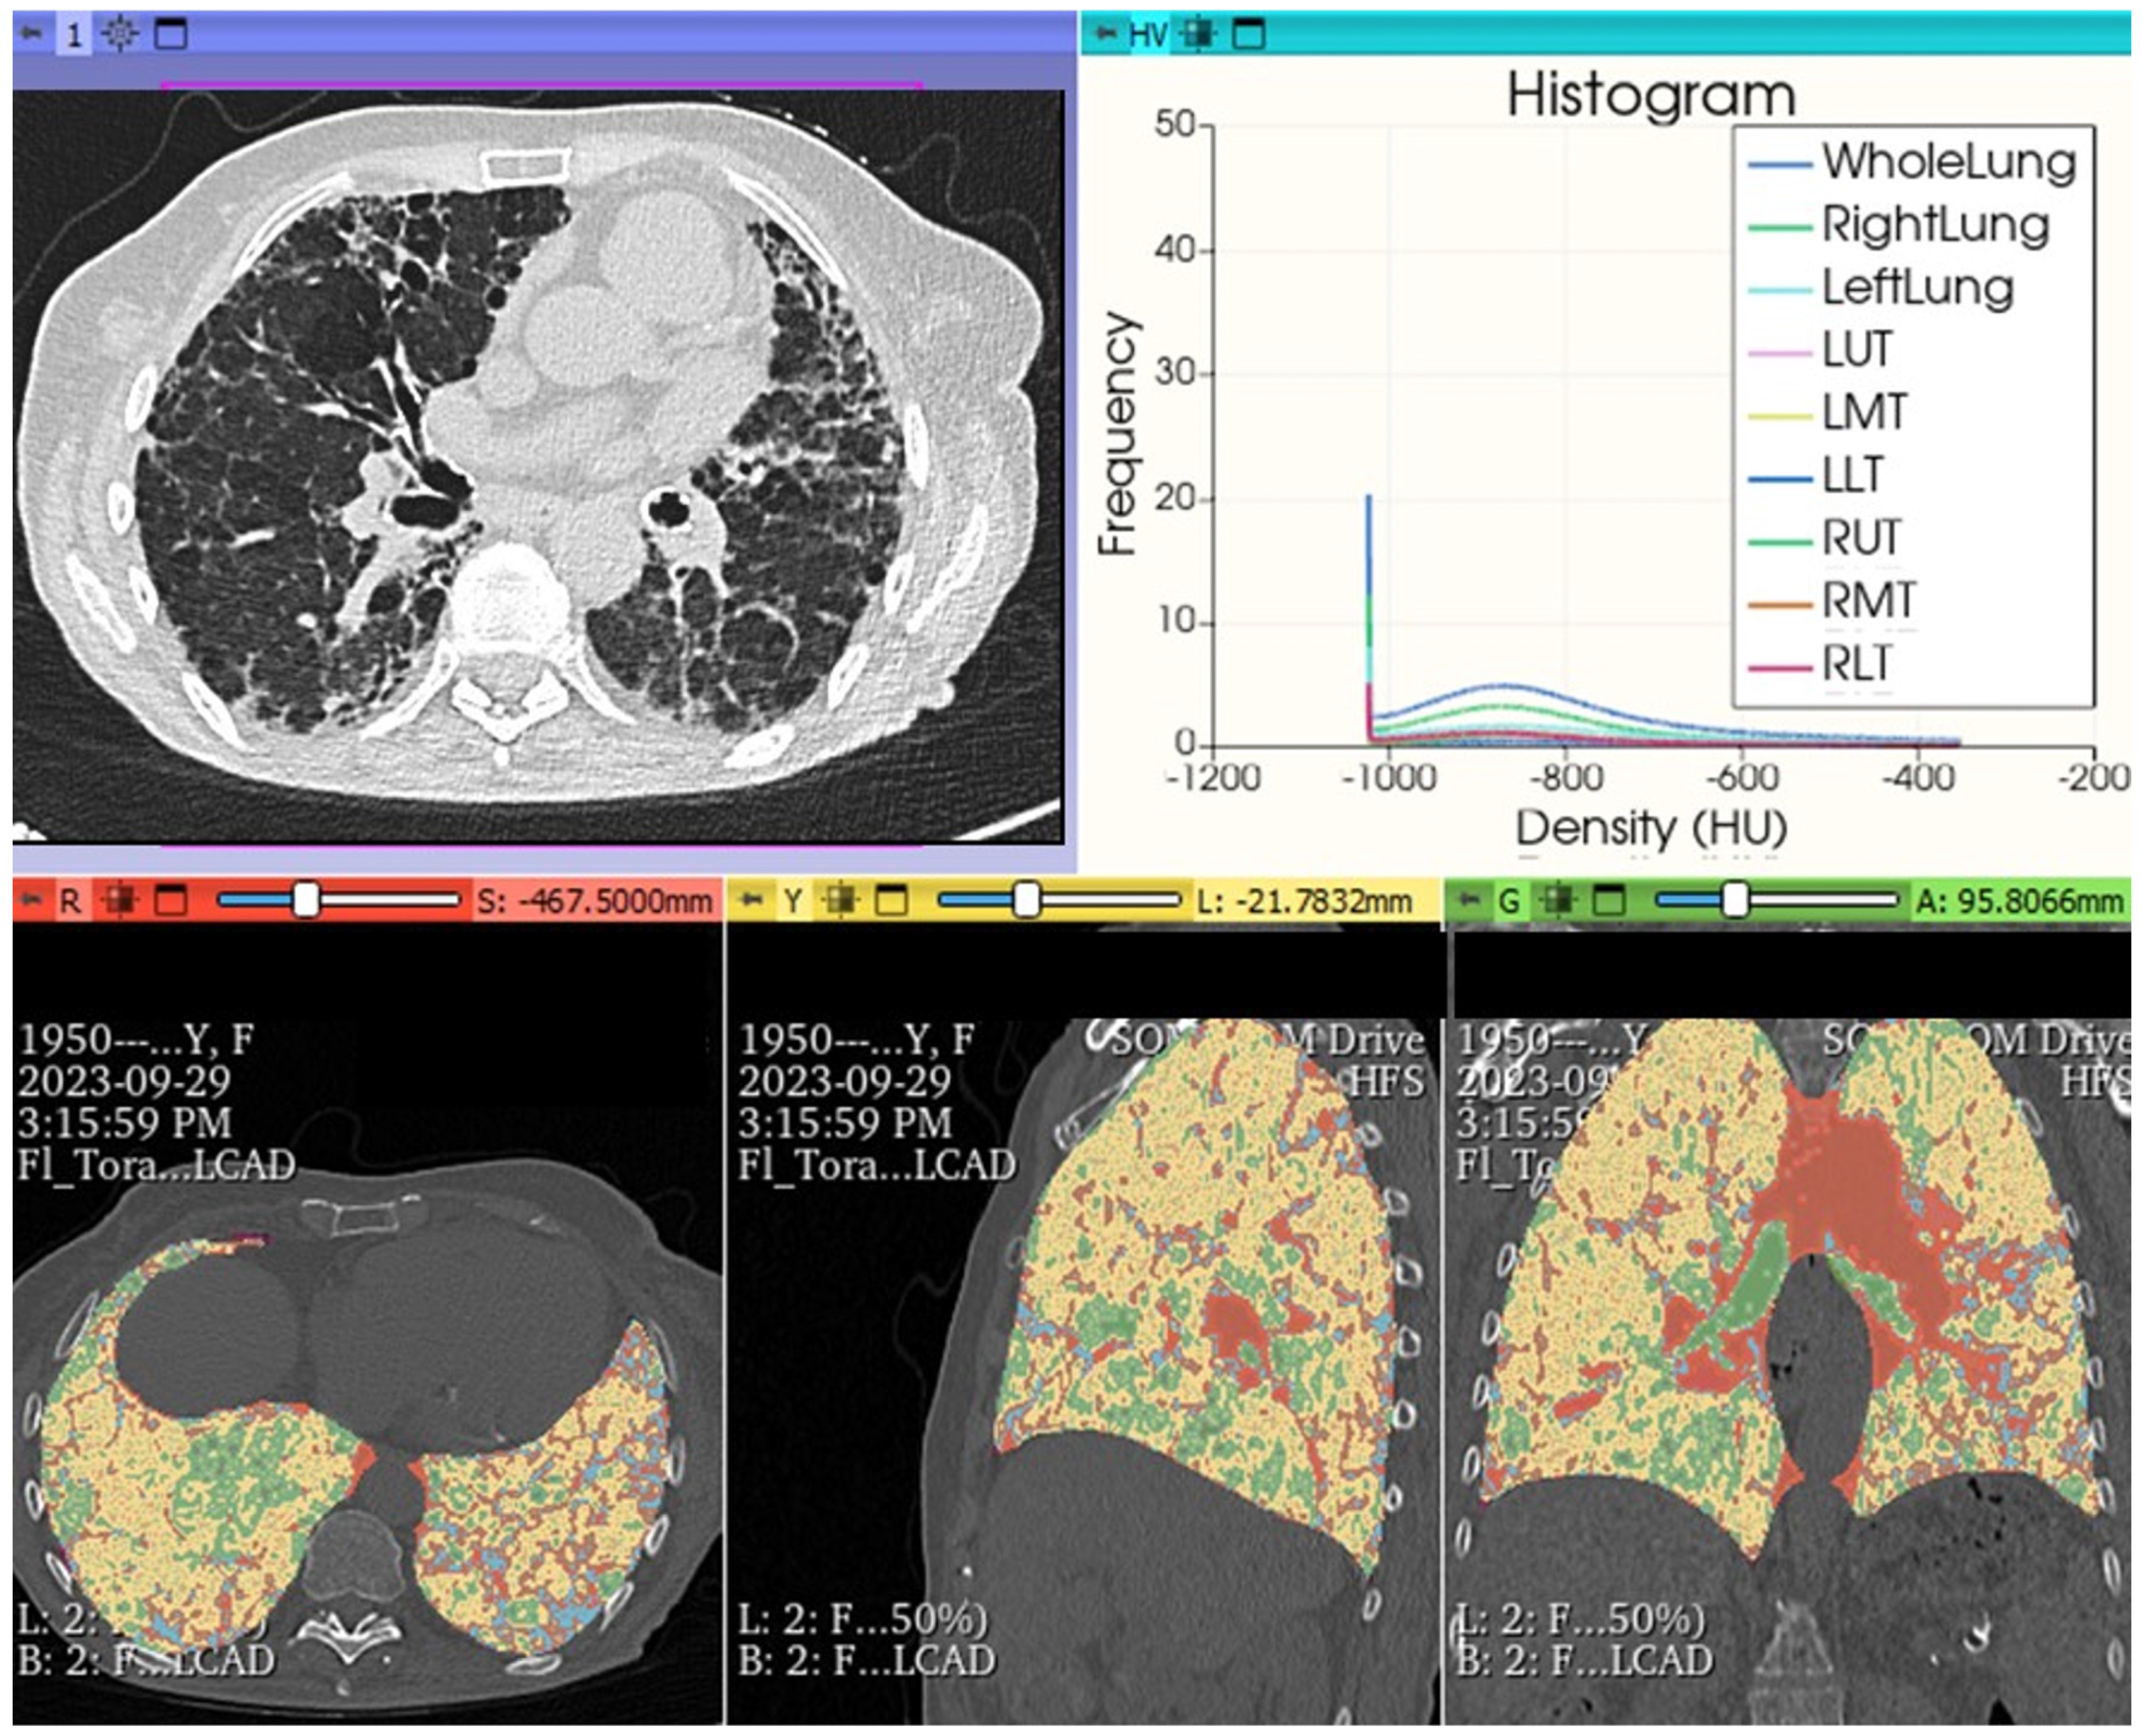

6. Beyond the Surface: Artificial Intelligence’s (AI) Role in Unearthing Hidden Patterns in ILDs Imaging

The growing attention on the evolving profiles of FHP forms correlated with an unfavorable prognosis is further directed towards the radiological imaging realm for a more precise definition of HRCT alterations, as well as therapeutically, with the opening to treatments for progressive forms of HP with anti-fibrotic drugs. The perspective of using both open-source and paid software has, in the last five years, opened horizons previously unimaginable: in ILDs, visual imaging is integrated with quantitative assessments and AI, involving in-depth analysis of HRCT morphological data. Thoracic volume can be extracted, segmented and interpolated with color-coded encodings in post-processing, analyzed comprehensively or for individual lobes of each lung, obtaining conclusive reports rich in numerical and quantitative/radiomic information. This allows for the integration of extremely objective parameters of fibrotic damage associated with clinical and functional data (in vivo biomarkers) and, finally, extrapolating new data to complement classical clinical and functional information. Therefore, a highly sophisticated analysis is possible, introducing classification diagnostic systems with AI, using deep learning algorithms and derived radiomic features. The increasing use of Convolutional Neural Networks (CNNs) for a possible not only diagnostic but also prognostic evaluation offers additional possibilities to explore the complex physio-pathobiological alterations of extremely complex diseases such as ILDs, although currently not yet usable in common clinical practice due to ongoing validation trials concerning the lack of in-depth and robust clinical and control studies (Figure 14). However, in the immediate future, these possibilities will allow for an exceptional approach beyond “visual power”, providing additional potential markers, most of which are not yet known but can further stratify the patient pattern with ILDs, allowing for the analysis of specific “features”, such as radiomics. Today, it is not yet possible to give a specific meaning to these [30,31,32,33,34,35,36,37,38,39].

Figure 14.

FHP pattern. Chest HRCT: histogram analysis and quantitative reprocessing in MPR on Slicer3D colorimetric scale. AI: radiomics first order features extracted by HRCT after analysis with AI algorithm pyradiomics: whole lungs LAA% −950:13.640; LAA% −910:23.190; HAA% −700:30.560; HAA% −500:16.243; Perc10: −969.000 mean: −719.705; kurtosis: 3.241; skewness: 1.787; ventilation heterogeneity: 0.915; mass 491.189; volume: 1.712; entropy: 2.5032189221693084 energy: 1795731501003.0; variance: 1655.8891640178702; uniformity: 0.18260469191135123.